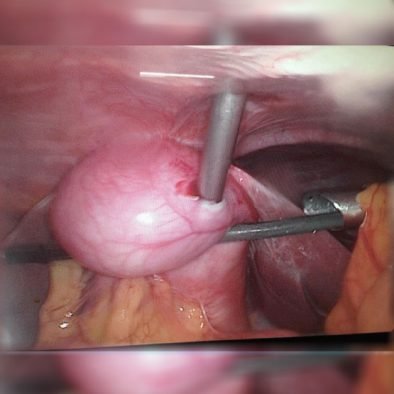

ByRL GYNAECOLOGY INSTRUMENTS

ByRL Uterine Manipulator

The fully visualization of the uterus and the adnexa is the important basis for a good gynecological laparoscopic surgery. An Uterine Manipulator that can be adjusted to different angles allows the operator to flex and rotate the uterus so that it can be brought into an optimal position.

Uterine Manipulator are available in 2 types :

- Uterine Manipulator “Marwah” type

- Uterine Manipulator “Sukhadia” type

Product Features :

- Made up of Medical Grade plastic / polycarbonate and Stainless steel.

- Fully reusable